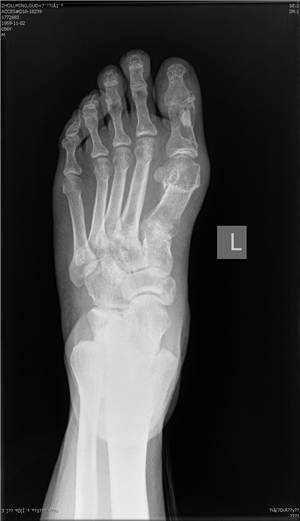

微创矫形方法术前(左)术后(右)X光对比